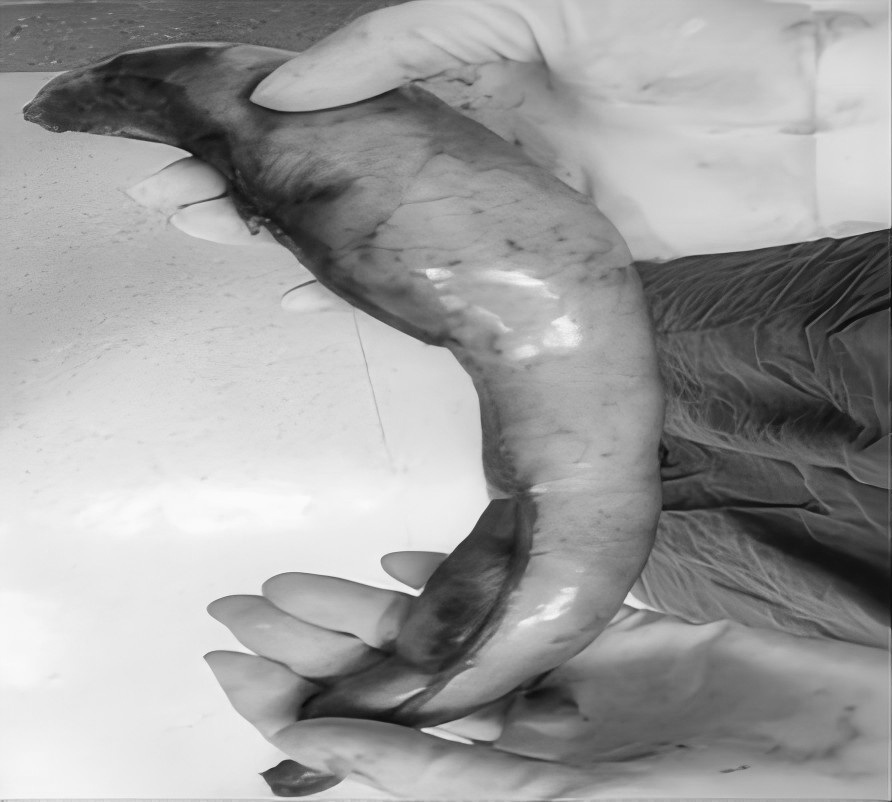

3月5日,贵州航天医院第51次晨读会由我院普外科主任、主任医师梁跃作学术交流,他以“腹腔镜下清扫No.253淋巴结的解剖问题”为题,全面讲解了No.253淋巴结的定义、清扫指征、清扫范围、相关解剖学知识等具体情况,并结合实际案例与图文对相关解剖进行了详细剖析,形象地展示了该区域复杂的解剖结构及在手术过程中可能遇到的解剖难点与要点。 普外科专家简介 梁 跃 普外科主任 主任医师 临床擅长:对普外科各类肿瘤手术具有丰富的临床经验。 毕业于遵义医学院,遵义市医学会小儿外科学分会常务委员,遵义市肛肠协会理事,遵义市医学会核医学分会(第二届)委员会委员;荣获第三期“黔医人才计划”优秀学员称号;主持市级课题1项,完成省级课题1项,在国内各类刊物上发表论文10余篇。 钱科洪 普外科 副主任医师 临床擅长:从事普外科临床工作30余年,对各类普外科疾病的诊治、乳腺、甲状腺、胃十二指肠、结直肠等疾病及疑难杂症具有丰富的临床诊疗经验。 毕业于遵义医学院临床医疗系,2009年前往中山大学附属第一医院微创外科进修学习,在国内各专业期刊发表论文数篇。 普外科简介 基本情况 贵州航天医院普外科成立于1968年,前身属于航天部O61基地3417医院外一科,3417医院、3427医院合并后更名为普外科,下设胃肠外科、肛肠外科2个亚专业科室,是中国疝病专科联盟单位,贵州医科大学附属医院胃肠外科专科联盟单位。开放床位40张,配备医护人员21人。 专科特色 普外科致力于胃肠及肛肠疾病的外科临床诊治及科研,以腹腔镜微创外科技术为本,形成以快速康复治疗胃肿瘤、结直肠肿瘤、小肠肿瘤、直肠脱垂、肥胖病、急腹症、各类疝、痔、瘘等专科特色,同时注重胃肠疾病尤其是结直肠恶性肿瘤的基础研究和临床转化研究,总体诊断和治疗水平在区域同级医院居于领先水平。 开展手术:腹腔镜下胃癌根治术,腹腔镜下袖状胃切除术,腹腔镜下胃肠道间质瘤切除术,腹腔镜下结、直肠癌根治术,胃癌、结直肠癌的精准治疗,腹腔镜下小儿疝气、成人疝修补术,腹腔镜下阑尾手术,内痔的硬化注射治疗及痔疮的微创治疗:ATH、PPH、TST,直肠脱垂的各种手术治疗,难治性伤口VSD技术,鼻胃肠管、肠梗阻导管置入术,肛肠术后间歇性导尿技术,并引进了中医适宜技术,也为各种化疗患者提供输液港安装,提高患者就医体验。 腹腔镜下腹股沟疝无张力修补术 腹腔镜下腹股沟疝 无张力修补术 腹股沟疝里金斯坦 (Lichtenstein)手术 PPH微创术治疗环状混合痔 黏连性或炎性肠梗阻-肠梗阻导管 腹腔镜袖状胃切除 腹腔镜阑尾切除术 腹腔镜阑尾肿瘤切除术 腹腔镜下结肠癌根治术 诊疗范围 胃肿瘤、结直肠肿瘤、小肠肿瘤、肥胖症、各类急腹症、腹部外伤、腹壁疝、便秘、直肠脱垂、痔疮、肛瘘、肛裂等胃肠、肛肠外科疾病。 end